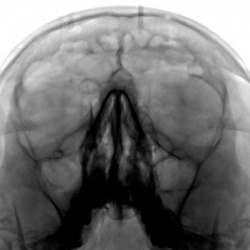

Пациент направлен на рентгенографию придаточных полостей носа оториноларингологом.

Пациент направлен на рентгенографию придаточных полостей носа.

Пациент направлен на рентгенографию придаточных полостей носа с профилактической целью ( по поводу операции на глазном яблоке).Фрагменты с увеличением.

Направлен отоларингологом 4